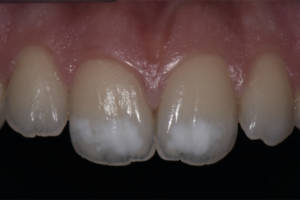

La paziente si presenta alla nostra osservazione per seduta di igiene orale professionale lamentando da sempre il suo disagio estetico per la presenza di due ampie macchie bianche in sede 11 e 21 e chiedendo se era possibile risolvere tale problematica (immagini 1-2-3).

Le foto a T-0 mettono in evidenza come l’inestetismo presente in sede 11 e 21 risulti particolarmente fastidioso per la paziente (immagine 1-2). Le immagini al follow-up a 6 e 12 mesi (immagini 4-5) mostrano il risultato soddisfacente del trattamento remineralizzante con un miglioramento della lesione dello smalto che ad oggi si presenta con un’area meno estesa e una riduzione dell’opacità generale delle lesione con un aumento della traslucenza.